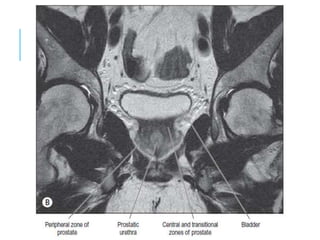

KIDNEY AND URETERS

MODALITY OF CHOICE